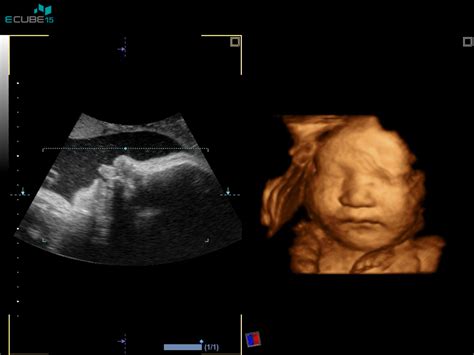

Postopek biopsije horionskih resic se izvaja pod stalnim ultrazvočnim nadzorom, kar zagotavlja natančno določitev položaja posteljice in višine nosečnosti. Zdravnik najprej z ultrazvokom pregleda lego posteljice in ploda. V kolikor je dostop do posteljice ustrezen, se s tanko iglo skozi trebušno steno nosečnice (transabdominalni postopek) ali skozi maternični vrat (transcervikalni postopek) odvzame vzorček tkiva horionskih resic. Preden se igla zapiči, se mesto vboda pogosto infiltrira z lokalnim anestetikom, da se zmanjša morebitna bolečina. S pomočjo ultrazvoka zdravnik natančno usmeri iglo do posteljice in odvzame košček tkiva, ki se nato pošlje v laboratorij na analizo. Sam postopek običajno traja le nekaj minut.